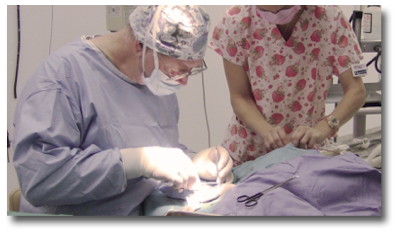

Keeping your pets healthy is our Number 1 priority, so we offer a range of services from annual or semi-annual wellness exams, to state of the art treatments and surgical procedures. Our surgical expertise is second to none in the Hawaiian Islands, and we receive referrals from throughout the South Pacific. We're happy to provide a FREE SECOND OPINION, should the need arise.

Advanced Services

Dr. Leadbeater is a pioneer of Advanced Veterinary Procedures and Surgeries not only on Oahu, but throughout the Hawaiian Islands. He also receives referrals from The Philippines and other Pacific Islands. He is proud to have been an early adopter for many new treatments and procedures to the islands.

Our spay and neuter program has stemmed from the need for affordable spay and neuter procedures. We have carefully researched the available options on Oahu, and have developed this program to address the need. While we may be an affordable alternative, we want to stress that our uncompromising standards for patient safety and quality of service are state of the art.

Day 1 -- We collect fat tissue, which is rich in stem cells. This is typically done with the animal under anesthesia.